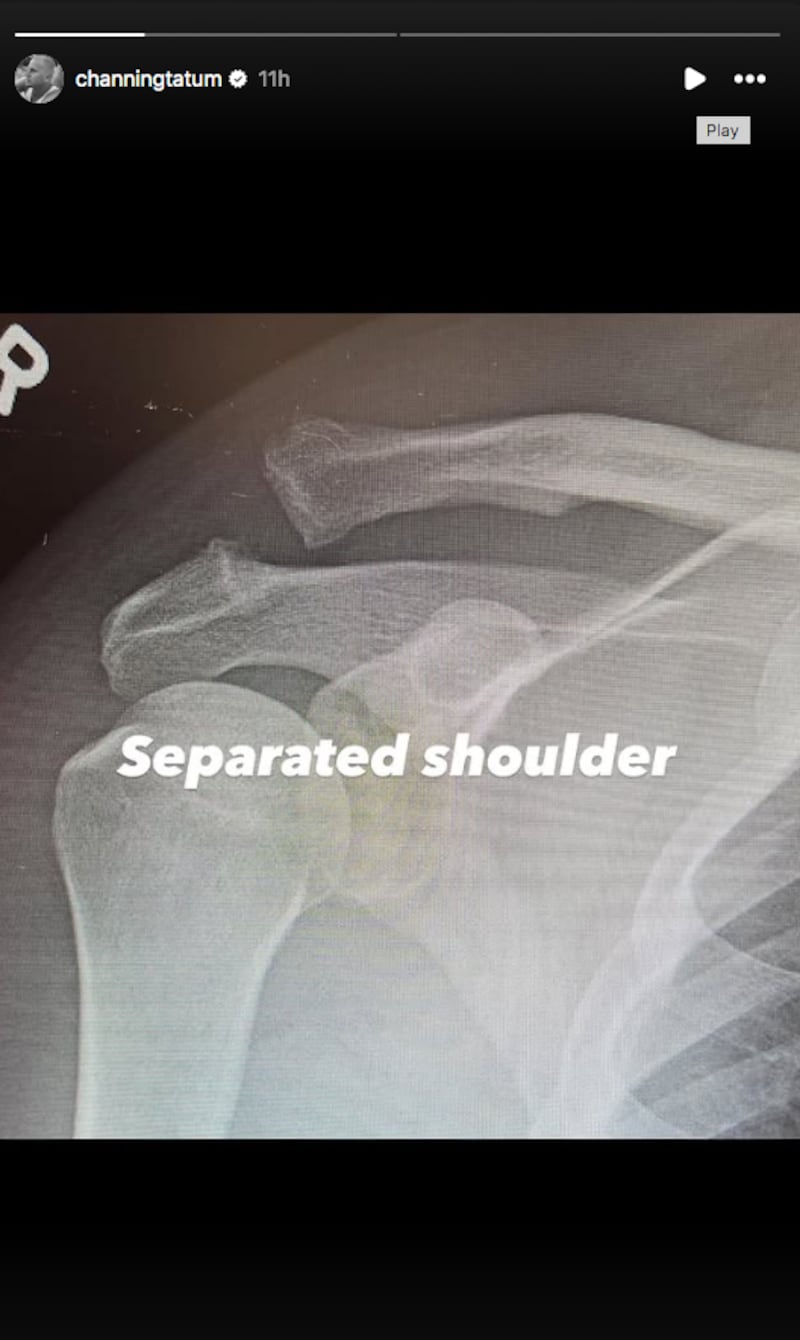

De acuerdo con lo que el propio actor compartió posteriormente en historias de Instagram, la cirugía estuvo relacionada con una lesión en el hombro. Tatum publicó dos radiografías: una etiquetada como “hombro separado” y otra donde se observa el resultado de la intervención.

En la segunda imagen, el actor bromeó sobre el procedimiento al describirlo como “hombro atornillado”, luego de que se apreciara un tornillo colocado para estabilizar la zona.